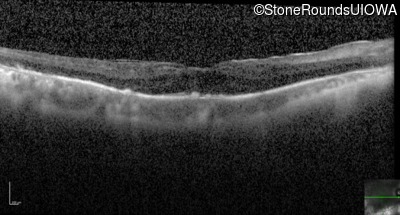

Optical Coherence Tomography - Right - 20/32

Exemplar / OCT Stack

OCT Stack